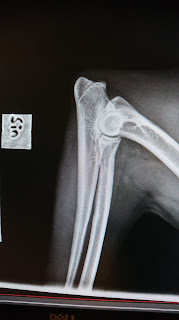

Filipendulas höfter och armbåge.